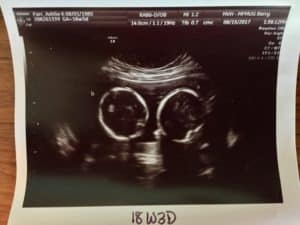

“Found out at 18 weeks because of a positive blood test for spina bifida. Turns out it was an extra baby making the blood test go wrong.”

∼ MK

Twins can typically be detected on ultrasound during the first trimester, usually around 6 to 8 weeks of gestation. In some cases, healthcare providers may be able to identify the presence of twins even earlier, especially with advanced ultrasound technology. The ability to visualize twins on an ultrasound depends on factors such as the clarity of the image, the position of the embryos, and the experience of the ultrasound technician.